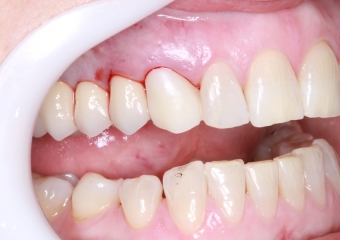

Foto frontal extra oral pré-cirurgica 03-10-16 - Clínica Cliniface

Foto frontal extra oral pré-cirurgica 03-10-16